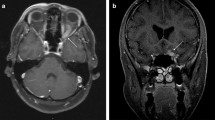

Sarcoidosis is a multi-system, non-caseating granulomatous disease of unknown etiology. Although spinal cord involvement is rare, it may cause severe neurological complications. We report the case of a 52-year-old woman who developed low back pain and a progressive flaccid paraparesis whose investigations revealed pulmonary and spinal sarcoidosis. To our knowledge, this is the first reported case of sarcoidosis of the conus medullaris and cauda equina diagnosed by an unusual enhancement pattern observed on magnetic resonance imaging with gadolinium. Biopsy of the lumbar nerve roots and of the lung revealed a non-caseating granuloma. Treatment with steroids and intensive rehabilitation resulted in remarkable functional improvement. Although rare, sarcoidosis of the conus medullaris and cauda equina should be considered in the differential diagnosis of flaccid paraparesis, particularly in patients with non-diagnostic evaluations.